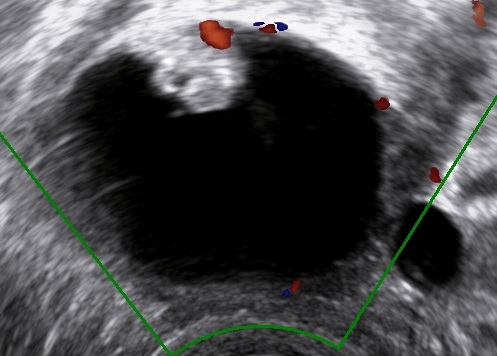

Presence of vascularized and irregular papillary projections in a unilocular cystic mass in the absence of other abnormal findings should arise the suspicion of a borderline ovarian tumor (1, 2, 3). The presence of multiple septa may hint towards a mucinous borderline ovarian tumor (1).

Vascularized, irregular papillary projection.